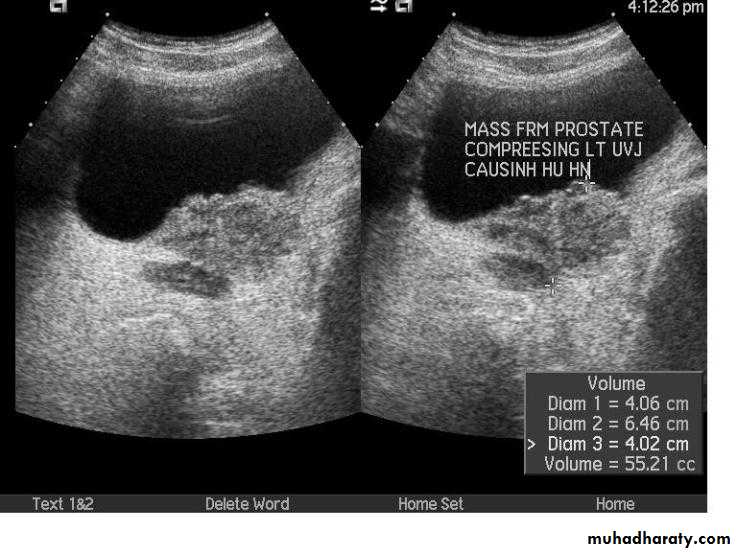

PROSTATIC Enlargement

Common cause of lower urinary obstruction . Either Benign prostatic hyperplasia or Carcinoma .Benign Hyperplasia :-

• IVU ( cystogram stage )

• * Elevated bladder base .• *Lower ureter elevated and curved (fish hook ).

• * Back pressure to both kidney & ureters .

• * Thick trabeculated bladder wall and diverticula formation .

• * Large size prostate produce filling defect like appearance .

• * Post-voiding residual volume .

* US can distinguish between BPH & Ca.